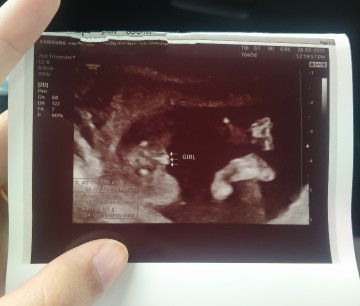

Baby girl

Kalau scan baby girl ni nanti keluar 50-50 sama ada girl atau boy. Tp nampak dlm gambar mcm clear tu girl

Saya scan mula mula babygirl , last last babyboy .. baby boy laa geng kita🥰🫠

uii jelasnya. i pergi 15w masih blm nampak burger. nampak tulang je leper

girl